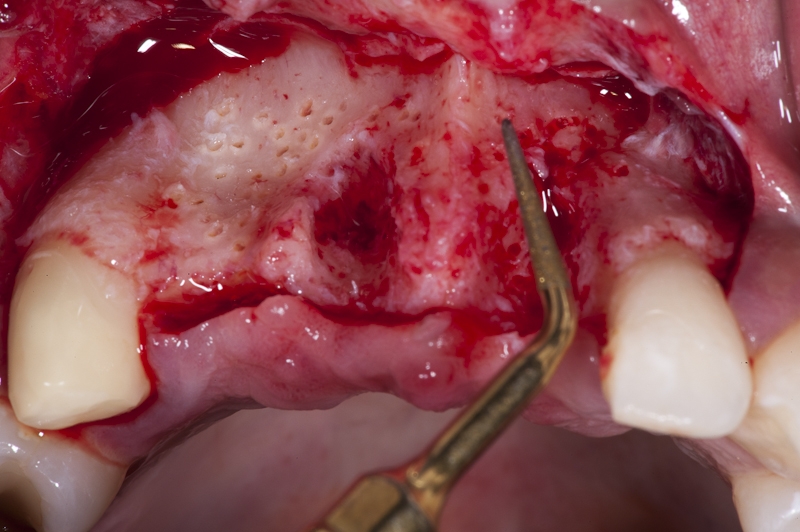

07/17 - Perforation of the vestibular cortical plate of the ridge with Piezosurgery to improve nutrition for the augmented site